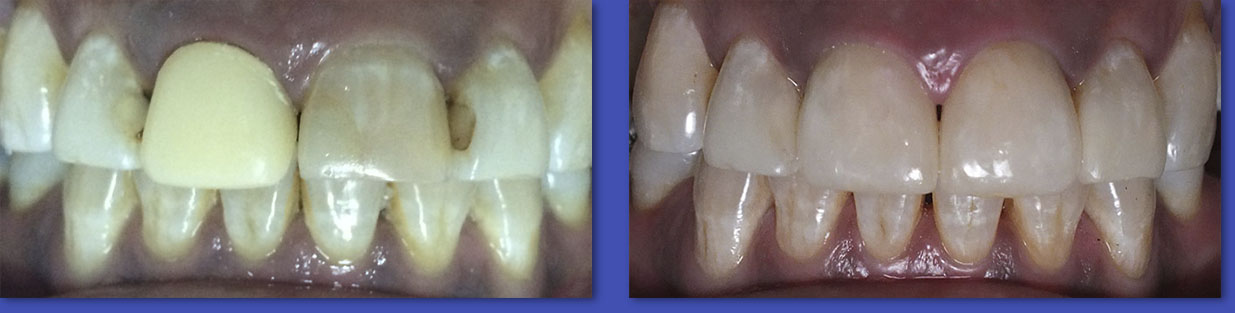

1.  OPERATORIA DENTAL

La Operatoria Dental se dedica a la restauración de los dientes dañados en forma parcial producto de caries, traumatismos  y otras lesiones no cariosas (atrición, abrasión, erosión, hipoplasias de esmalte, etc.). Hoy en día estas restauraciones se realizan en material de resina llamados “composite” que imitan el color del diente y han dejado casi obsoletas a las restauraciones metálicas y amalgamas.

ANTES

DESPUÉS